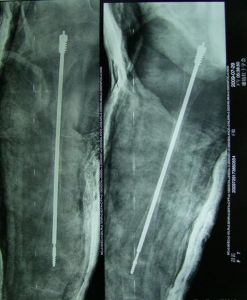

2、對骨折的治療同正常人。但骨折癒合迅速,固定期可短。

3、在矯正畸形方面,以防止再骨折為主。如皮質太薄,手術有困難時,可用異體骨移植。